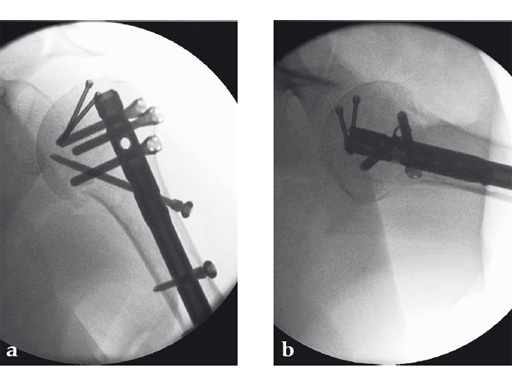

The tuberosities have been reduced and fixed using intertubercular sutures (Fig 4). To reconstruct the medial support a calcar screw has been used. This determines the height of the nail. Therefore a 1 cm end cap has been used to get support for the proximal end of the nail in the part of the bone with the best bone quality.

The patient was operated on in beach chair position. For the exploration of the radial nerve, a limited anterolateral approach was used. The nerve was mobilized and retracted laterally. An anterolateral approach to the proximal humerus was performed. The supraspinatus showed a small acute rupture without retraction. The supraspinatus tendon was split to get access to the insertion area on the humeral head. A 270 mm long MultiLoc Humeral Nail of 8.5 mm diameter was inserted under visual and x-ray control to the desired endpoint. Reduction of both the proximal and the distal humerus fracture was anatomical. In the lateral view there was a small gap, and it was decided to apply compression after distal locking (Fig 12). Proximally, three MultiLoc screws were inserted and a 2 mm end cap was placed. Finally, the supraspinatus rupture was reconstructed with transosseous sutures and secured with an augmentation plate. The posterior greater tuberosity fracture was secured with Fiber Wire to the MultiLoc screws. Fig 13 illustrates the definitive fixation.